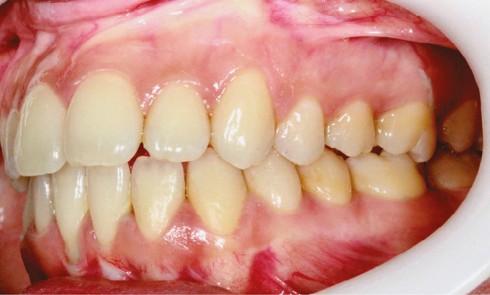

Article réservé à nos abonnés Prise en charge orthodontique et parodontale de migrations secondaires

Situation clinique Une femme âgée de 33 ans, sans antécédents médico-chirurgicaux notables, consulte pour la correction de l’égression de son...